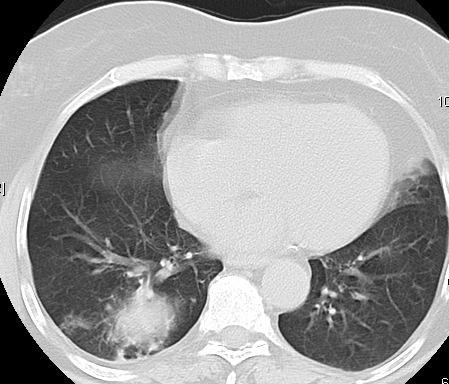

Grip H1N1

Pokazaću samo drastične nalaze kod gripa H1N1, to je znači onaj grip koji je izazvao epidemiju Španske groznice i epidemiju 2009. godine koja još uvek nije prestala (svake godine imamo makar 15%).

Nisu svi pacijenti imali ovakve nalaze, pokazujem one koji su imali tešku kliničku sliku. Kod gripa se sve odvija obično u 7 dana. Kao što se vidi zapaljenje je bilo jednostrano, uglavnom. Ali, kada je dolazilo do pogoršanja onda je centralno obostrano dolazilo do edema pluća.